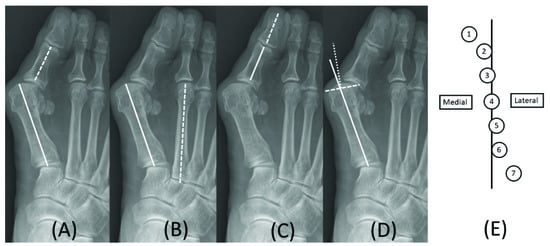

Angular measurement was completed in the pre- and post-operative weightbearing foot anterior–posterior plain radiographs. The pre-operative images were taken within one month from operation day, and the post-operative images were taken at post-operative six months. The hallux valgus angle (HVA), intermetatarsal angle (IMA), hallux valgus interphalangeus angle (HVIP), distal metatarsal articular angle (DMAA), and sesamoid position were checked (Figure 1) [9].

Figure 1. Preoperative angle measurements in a plain radiograph. Hallux valgus angle was defined as the intersection angle made by the longitudinal axis of the first metatarsal (solid) and proximal phalanx (dash) (A); The intermetatarsal angle was the intersection angle made by the longitudinal axis of the first (solid) and second (dash) metatarsal (B); Hallux valgus interphalangeal angle was the intersection angle made by the longitudinal axis of proximal (solid) and distal (dash) phalanx (C); Distal metatarsal articular angle was the intersection angle made by the longitudinal axis of the first metatarsal (solid) and bisecting line (dot) of the articular surface (dash) (D); The sesamoid position was evaluated with medial sesamoid position to longitudinal line of the first metatarsal (E).